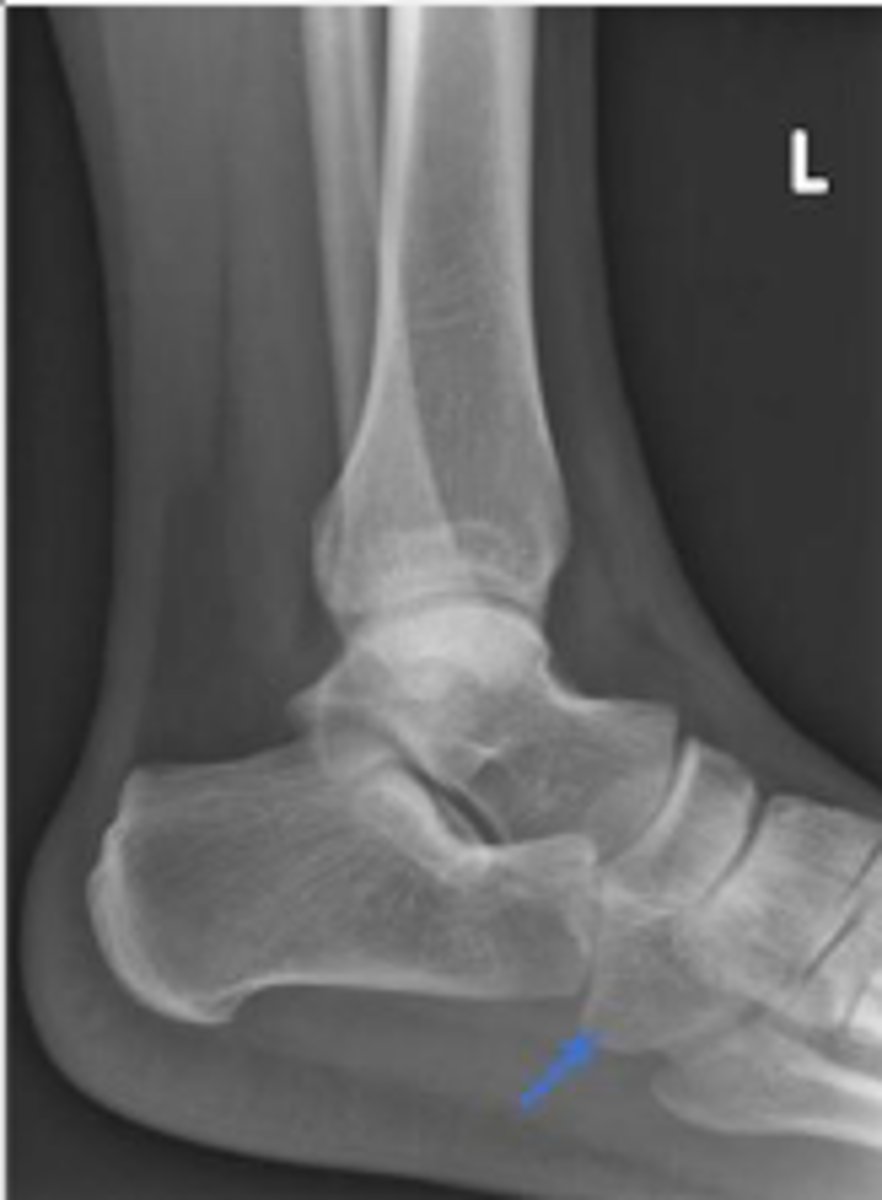

Achille's tendon of the left ankle

What are the arrows pointing to?

Cuboid of the left ankle

What is the arrow pointing to?

Heel pad measurement

What is the name of the assessment?

Females: average 19mm (maximum of 23mm)

Males: average 19mm (maximum of 25mm)

What is the normal range for the assessment?

Achille's tendon thickness

4-8mm

Yes

Is the assessment within normal limits?

Overuse, ill-fitting shoes, tendinosis/tendinitis,

rheumatological diseases, etc.,

Name 2 conditions that may result in an increase in the measurement beyond the upper limit of normal ?